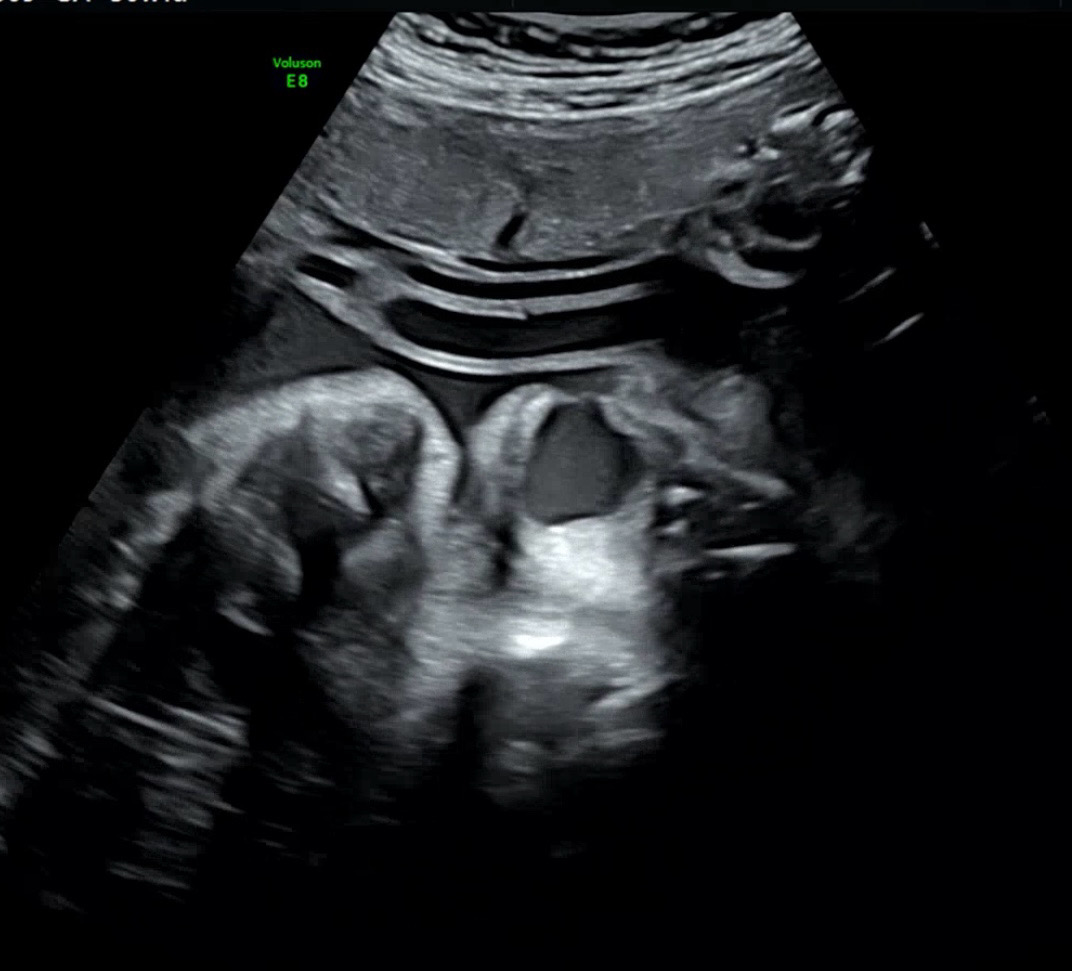

촘파에서 아기 하품 포착했어요🥱

하품하는게 너무 귀엽고 하찮고 신기해서 공유합니다 ㅎㅎㅎㅎㅎ 양수가 안들어가나? 궁금하기도 했어요😂